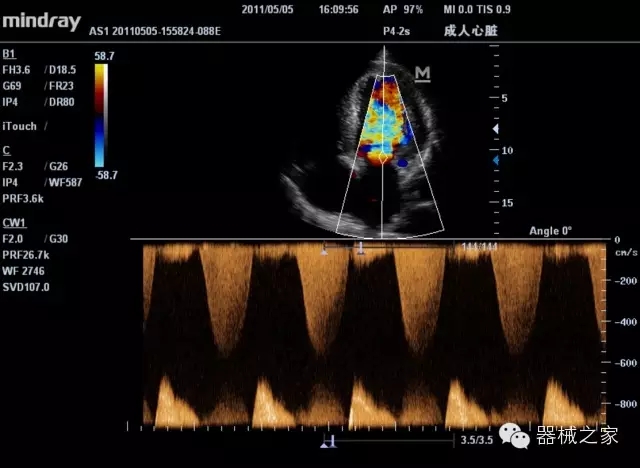

經(jīng)典產(chǎn)品:M7(星鉆)

臨床圖片賞析

產(chǎn)品特點(diǎn)

·裝載有采用Multi-Core多核處理的非嵌入式平臺,成像效率大大提高,并且能夠給用戶帶來高速、多任務(wù)并行信號處理體驗(yàn);

·優(yōu)秀的圖像效果、強(qiáng)大的功能體驗(yàn)、豐富的探頭選擇、合理的便攜式設(shè)計(jì),全中文顯示及病人管理界面,使得M7在任何場合、任何時(shí)候都能快速響應(yīng)更好的心血管、腹部、婦產(chǎn)、小器官等常規(guī)超聲檢查以及肌骨、神經(jīng)、顱腦、術(shù)中等新興領(lǐng)域的使用需求;

8倍波束并行處理系統(tǒng)

·在便攜式緊湊平臺上采用更多倍波束并行接收信號處理模式,無論二維還是彩色血流圖像狀態(tài)下,擁有更靈敏的回波頻移捕獲能力,大大提高時(shí)間分辨率,尤其使得心血管表現(xiàn)更為突出;